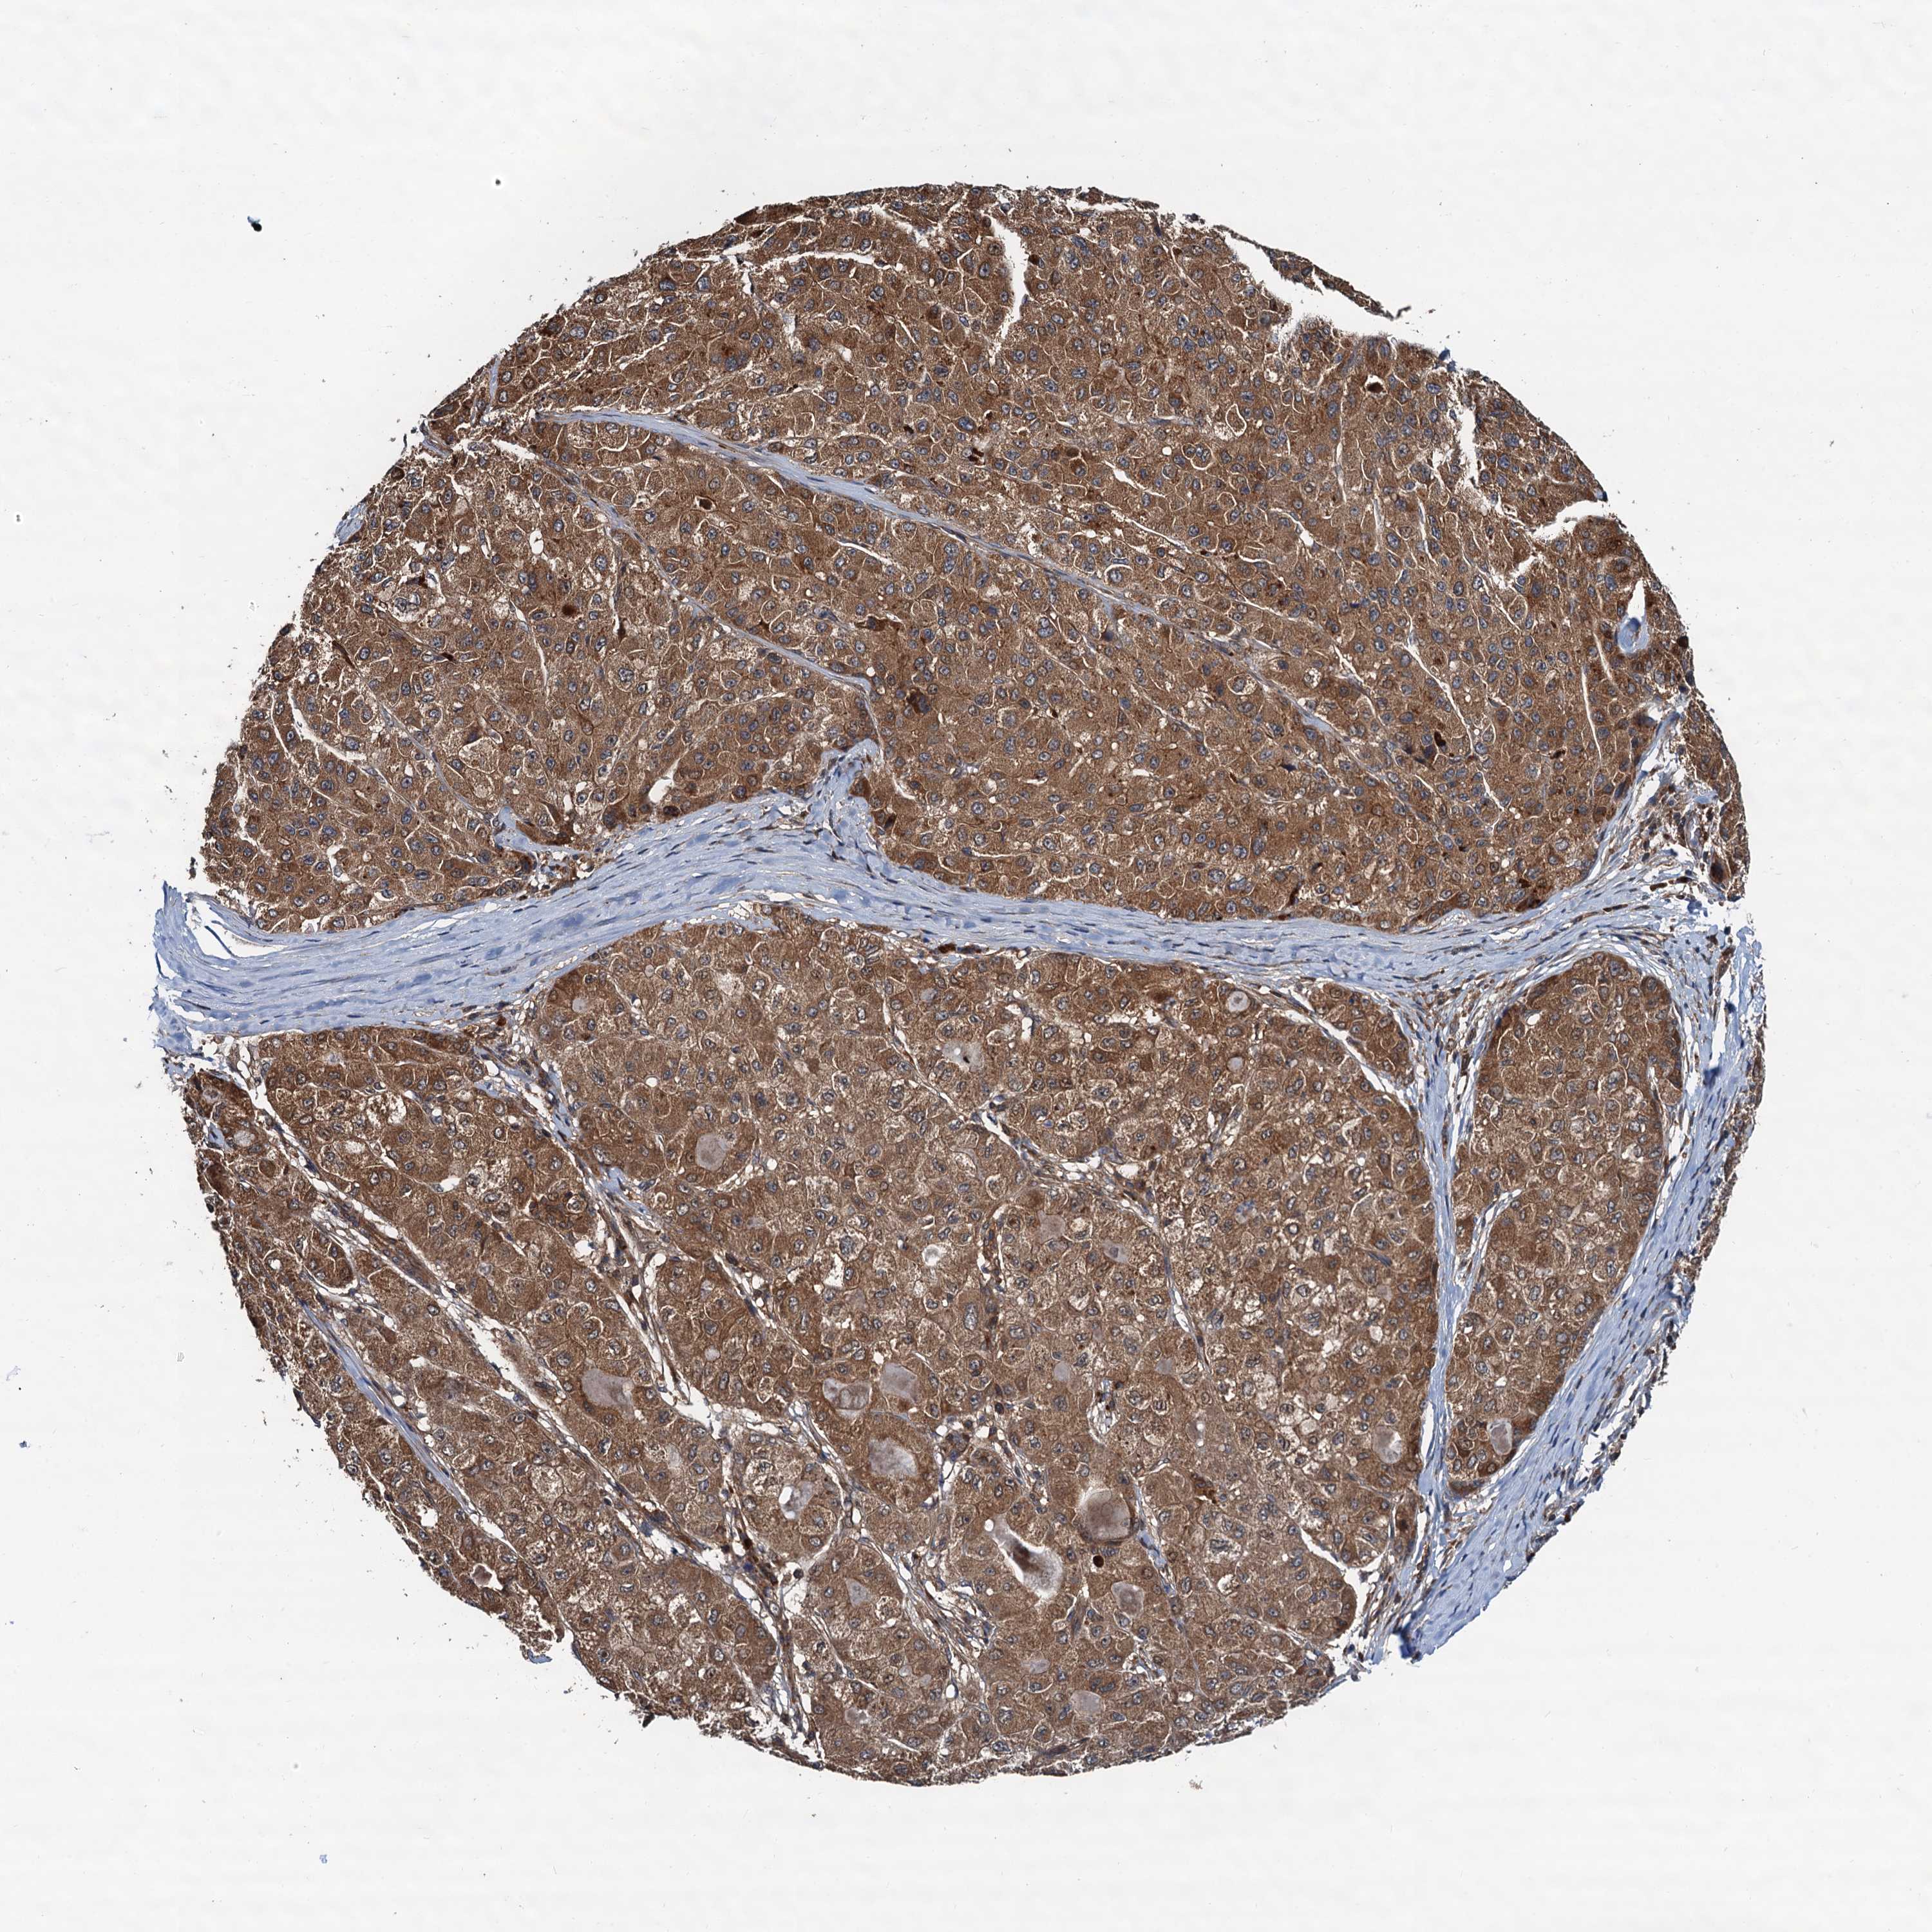

LIVER CANCER - Protein expressioni

A mouse-over function shows sample information and annotation data. Click on an image to view it in a full screen mode. Samples can be filtered based on level of antibody staining by selecting one or several of the following categories: high, medium, low and not detected. The assay and annotation is described here.

Note that samples used for immunohistochemistry by the Human Protein Atlas do not correspond to samples in the TCGA dataset.

Antibody stainingi

Antibody staining in the annotated cell types in the current human tissue is reported as not detected, low, medium, or high, based on conventional immunohistochemistry profiling in selected tissues. This score is based on the combination of the staining intensity and fraction of stained cells.

Each image is clickable and will lead to virtual microscopy that enables deeper exploration of all samples and also displays staining intensity scores, fraction scores and subcellular localization as well as patient and tissue information for each sample.

Antibody HPA039371

Antibody HPA040174

Staining

High

Medium

Low

Not detected

Intensity

Strong

Moderate

Weak

Negative

Quantity

>75%

75%-25%

<25%

None

Location

Nuclear

Cytoplasmic/membranous

Cytoplasmic/membranous,nuclear

Cholangiocarcinoma

Carcinoma, Hepatocellular, NOS